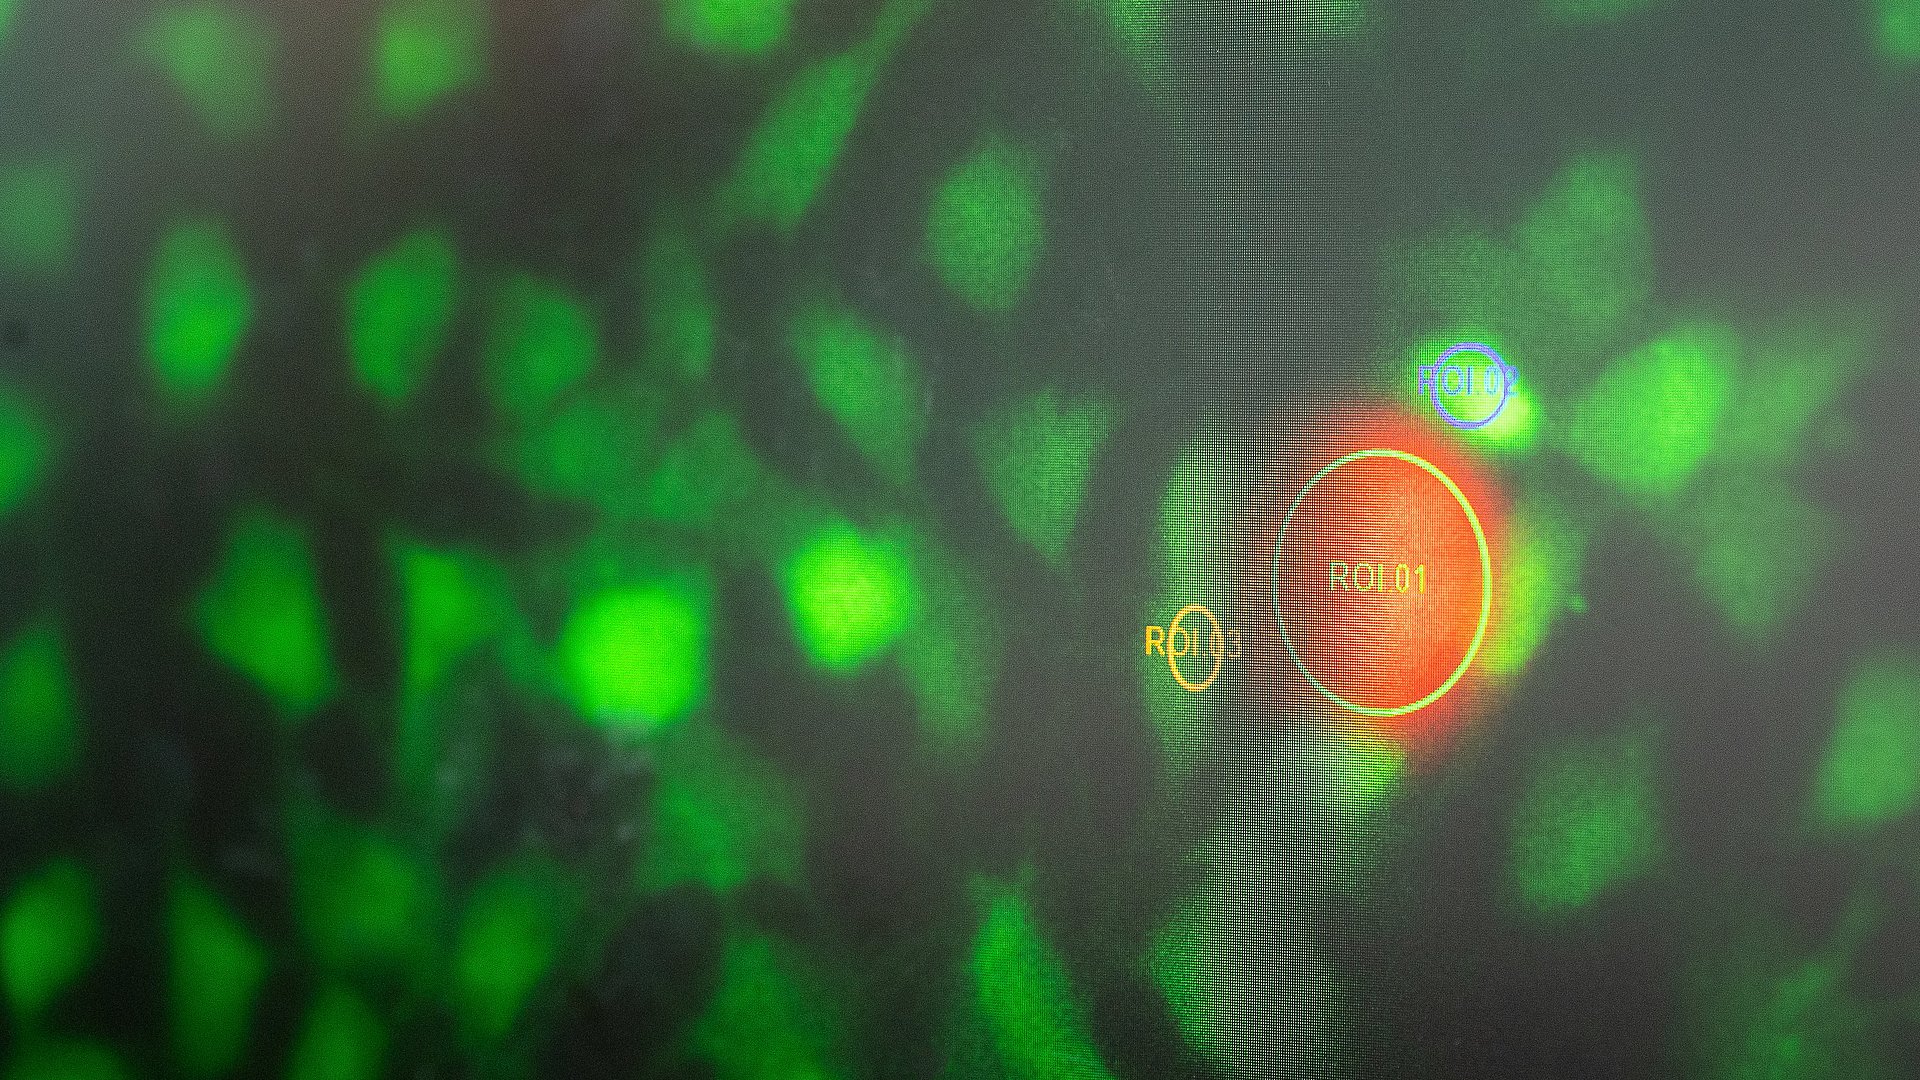

Ein Nanoroboter (orange) im Labor von Prof. Berna Özkale Edelmann Astrid Eckert / TUM

Ein Nanoroboter (orange) im Labor von Prof. Berna Özkale Edelmann. Mit solchen winzigen Robotern und sogenannten smarten Mikrogelen will die Wissenschaftlerin die Entwicklung von Stammzellen beeinflussen. Dieses und acht weitere Forschungsprojekte werden künftig mit ERC Starting Grants gefördert.

Prof. Dr. Berna Özkale Edelman

Das Ziel von Prof. Berna Özkale Edelmann ist, Stammzellen in Herzzellen zu verwandeln und damit Menschen zu helfen, die unter den Folgen eines Herzinfarkts leiden. Für ihren Forschungsansatz nutzt die Professorin smarte Mikrogele. Sie arbeitet nicht mit originalen Stammzellen, die aus befruchteten Eizellen gewonnen werden, sondern so genannten induzierten pluripotenten Stamzellen (iPSC). Diese „Ersatzstammzellen“ werden aus Hautzellen gewonnen, die gentechnisch verändert wurden. Diese iPSC bringt Özkale Edelmann in eine Zellumgebung ein, die sie selbst geschaffen hat. Sie baut quasi die Lebensumgebung eines Herzens nach, mit dessen mechanischen und dynamischen Eigenschaften. Die Viskosität und andere Eigenschaften der Mikrogele können variiert und damit Einfluss auf die Ausdifferenzierung der Stammzellen genommen werden. Das passiert auf der so genannten µStemGel-Plattform, mit deren Hilfe sie herausfinden will, welche Signale dazu führen, aus einer Stammzelle eine Herzzelle zu machen.

Berna Özkale Edelmann ist Professorin für Nano- und Microrobotics und Mitglied des Munich Center for Machine Intelligence (MIRMI) und des Munich Institute of Biomedical Engineering (MIBE).